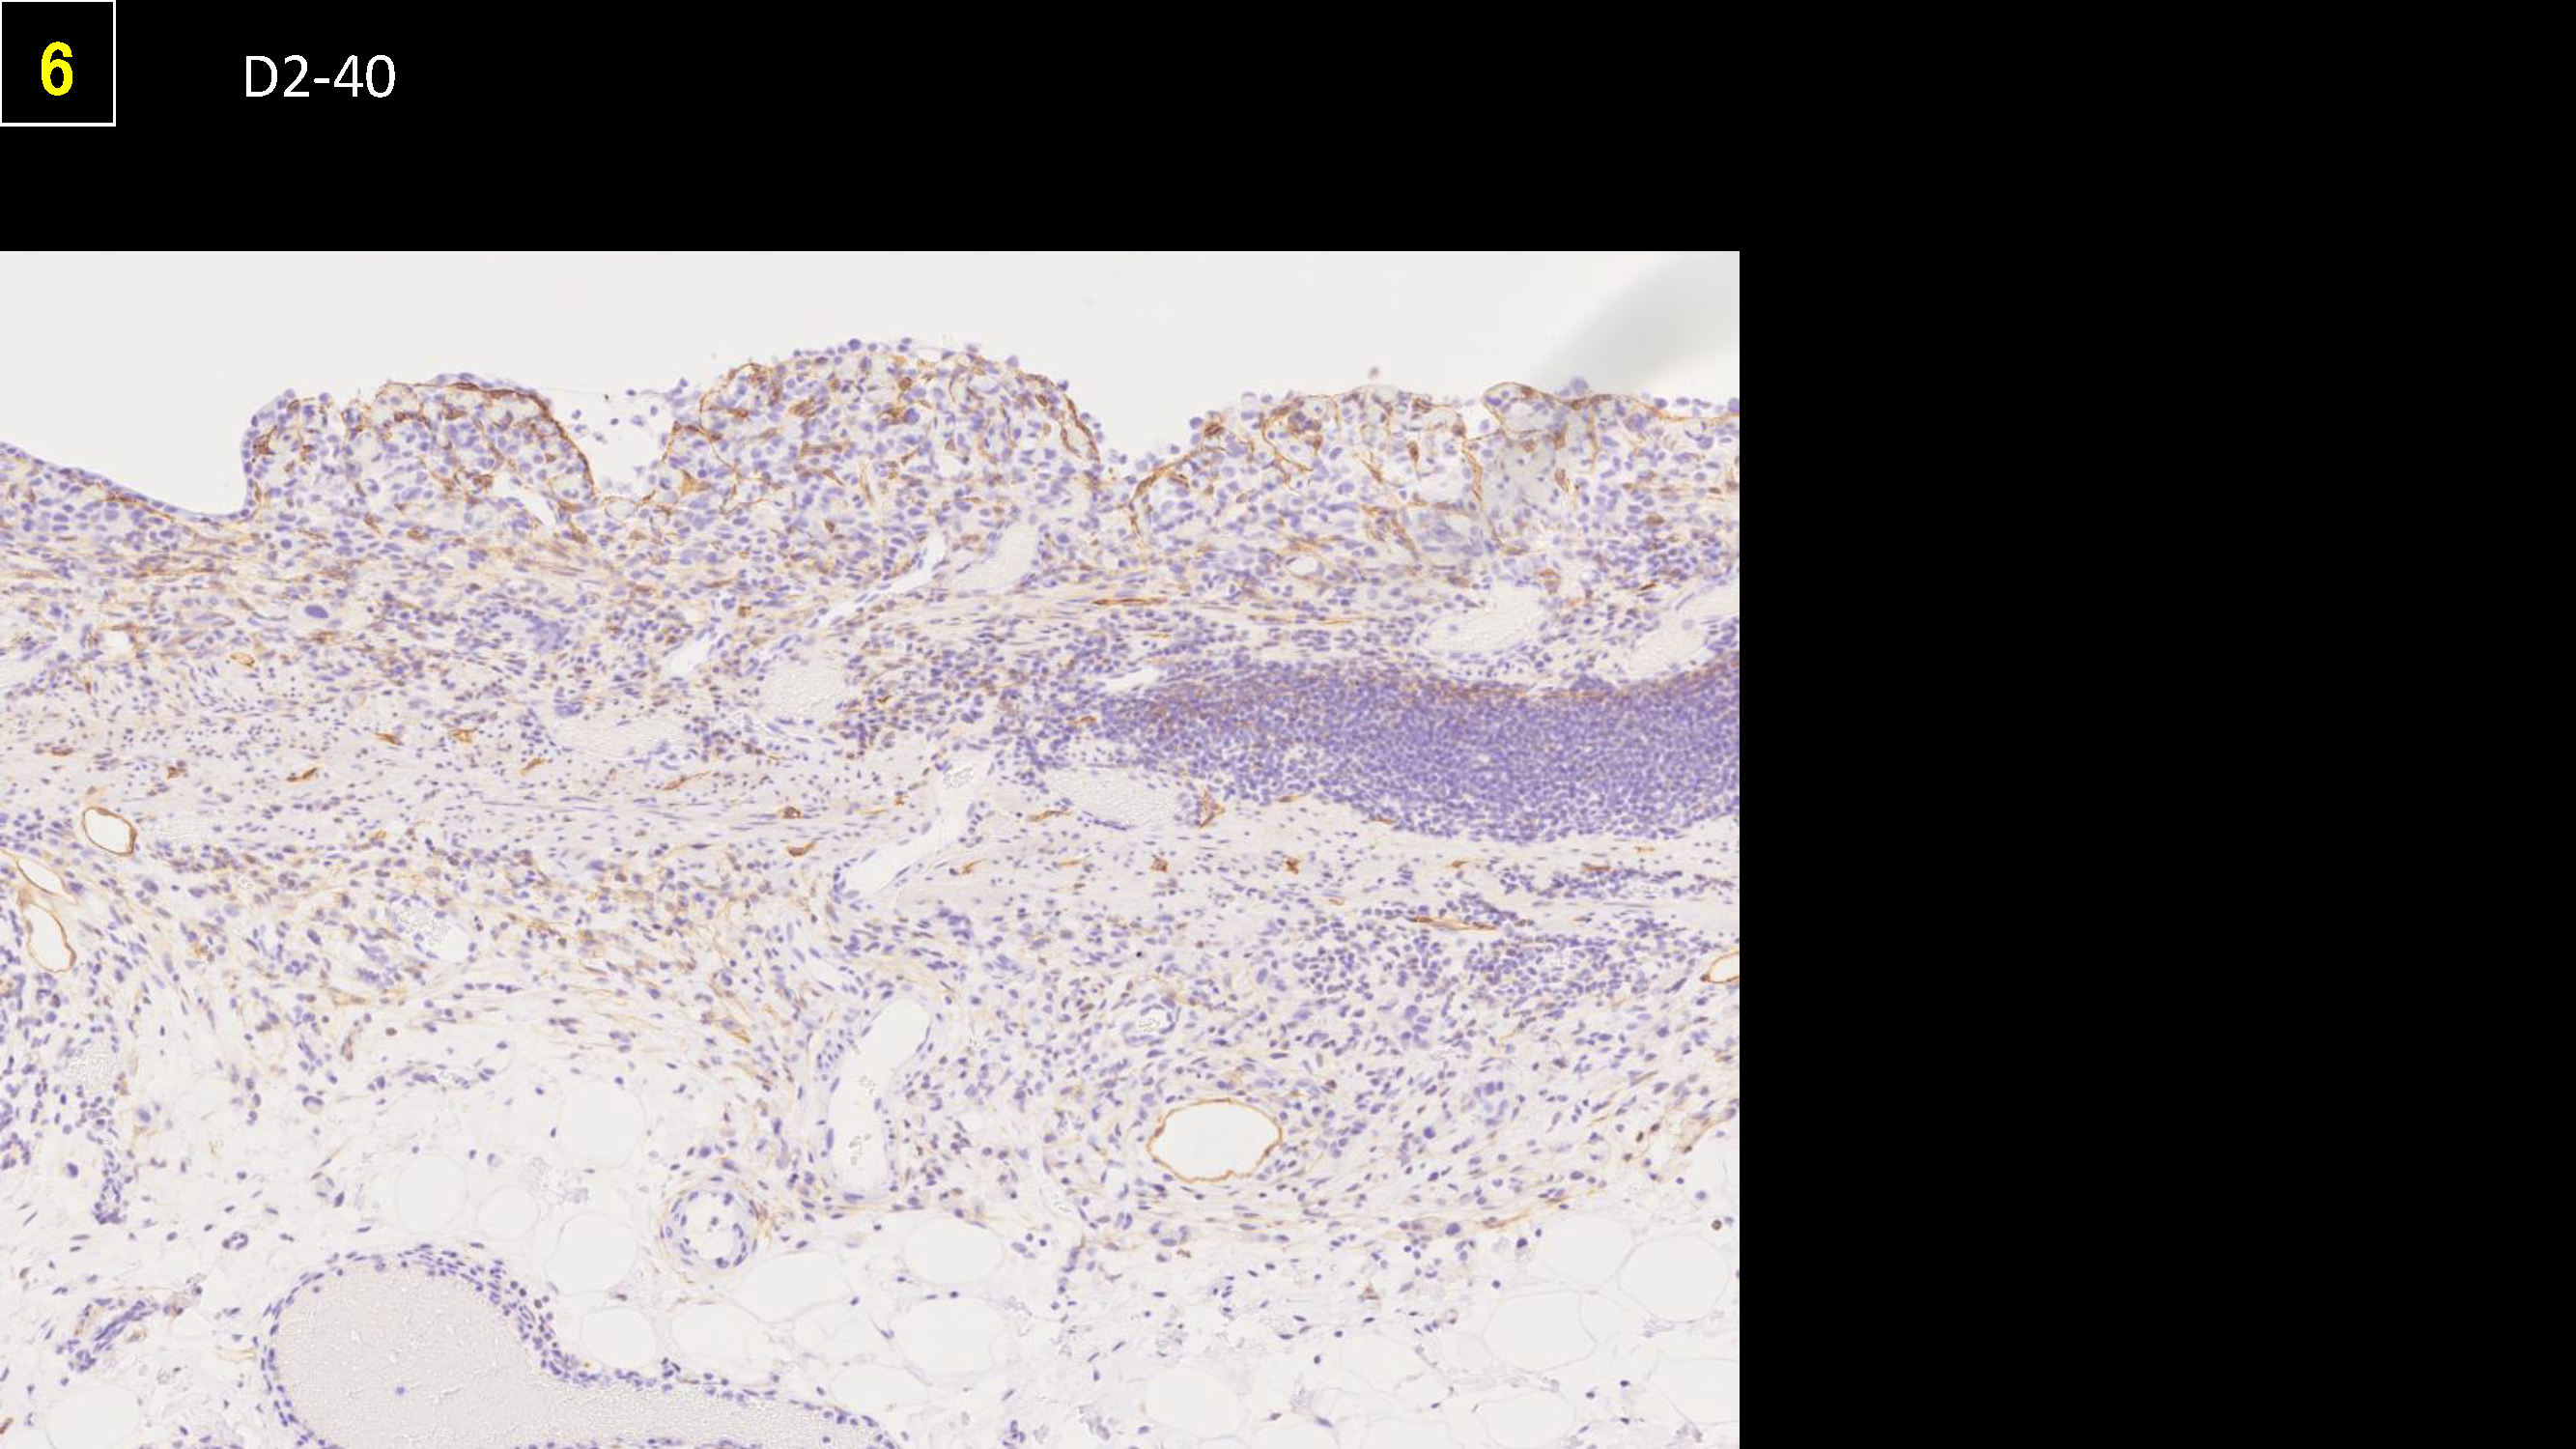

ホーム > 診療科・部門案内 > 消化器センター 消化器内科 > 消化管Mapping > 消化管Mapping~胃~ > 消化管Mapping~胃~ 2025.9.10